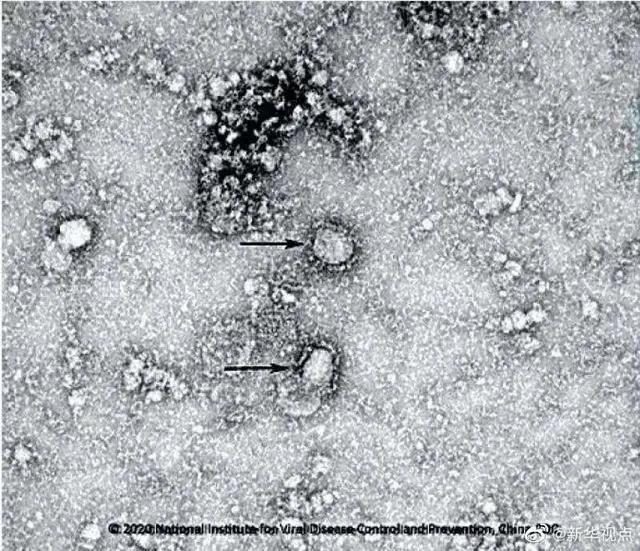

新冠病毒主要通过病毒表面的刺突蛋白Spike与人体的ACE2受体结合,来感染人类。S蛋白像一把钥匙,ACE2受体像一把锁,钥匙开锁后,病毒进入细胞。开发疫苗的主要目标,是阻止钥匙打开锁,以防止病毒感染细胞。科学家们的基础研究能帮助人们找到新冠疫苗的靶点,找到阻止钥匙开锁的方法。

而最新研究显示,新冠病毒是高度糖基化的球形颗粒,有着庞大的结构,至少有66个糖基化位点!新冠病毒的糖基化位点至少是艾滋病毒的2倍,这也意味着疫苗开发工作异常艰难。